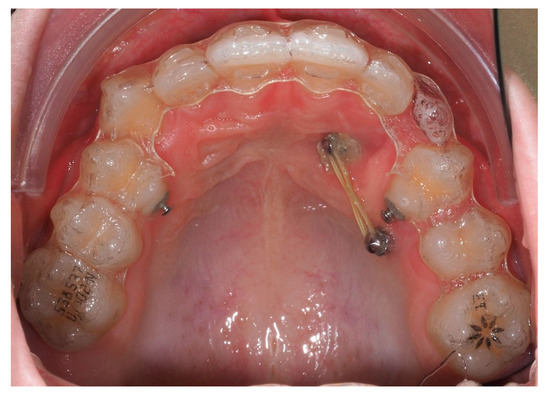

Following initial distalization, a sectional fixed appliance was bonded from tooth 11 to 26. On tooth 24, a bracket with a metallic ligature was used to support Class II elastics. Mini-tubes were bonded on teeth 22, 25, and 26, and the aligners were trimmed accordingly (Figure 16). A ligature wire connected the palatal button on the canine to a 0.014” nitinol archwire (Figure 17).

Figure 16.

Sectional fixed appliance from teeth 11 to 26, with support for Class II elastics to improve sagittal relationship; 14 months after the surgery.

Figure 17.

Ligature wire attached to a 0.014” nitinol archwire on the palatal surface of the canine; 14 months after the surgery.